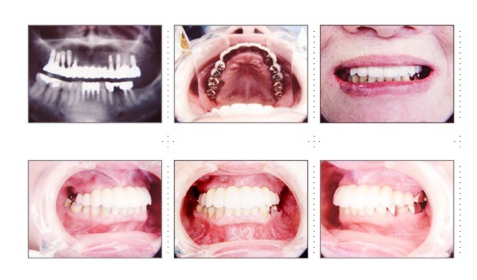

症例7

69才 女性

上顎骨がかなり減っていて、骨質・骨量共にインプラント治療には難しいケースです。

CT撮影後、埋入シュミレーションソフトで十分に検討します。このようなケースを成功させるには、患者さんの理解と協力が必要です。 下顎前歯が前突している為、抜髄しポーセレン冠で内側に配列。上顎前歯部・小臼歯部付近は骨幅が狭く、苦肉の策としてミニインプラントを使用。インプラントアバットメントの平行性、前歯の配列を考えると一般的には床を付けたインプラント義歯となります。装着感、審美性を考慮してブリッジにこだわりました。